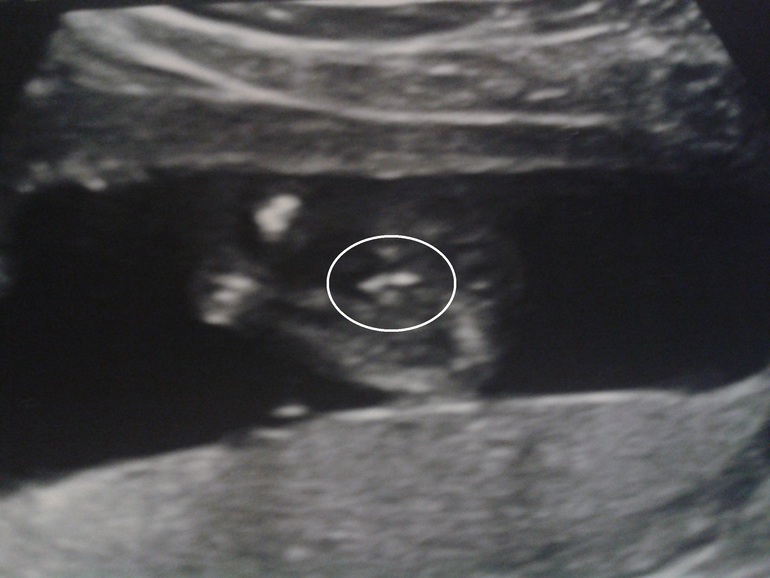

хотела сделать ДНК тест на раннее определение пола. Давно еще вычитала что в нашем городе есть лаборатория исследований ДНК,которая проводит этот анализ. Дай,думаю,позвоню. узнаю цену и их график "новогодний", т.к. 7 эмбриональных недель (которые являются минимумом для анализа)у меня выпадают на 27-28 декабря. Звоню ж вся такая довольная,в предвкушении...а консультант мне:

блин так не хочу до 16 недель ждать(((